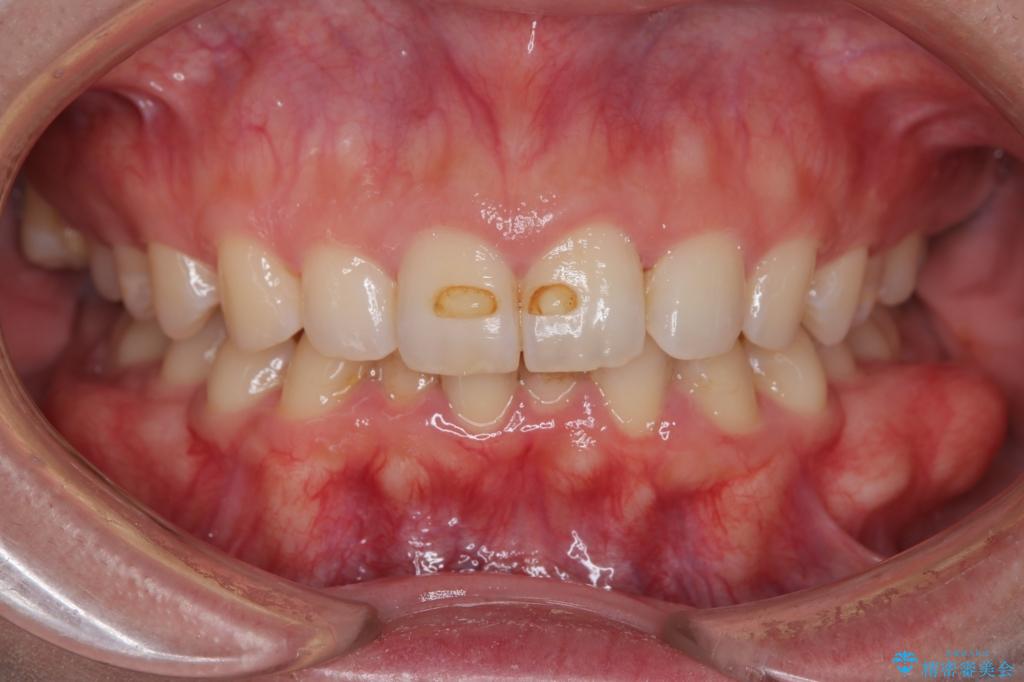

【インビザラインとワイヤー矯正】がたつきと噛み合わせを改善!

- 下の歯のがたつきを主訴に来院されました。

下の歯のがたつきと右の奥歯の噛みあわせ改善するために治療計画を立てることにしました。

噛み合わせをよくするために、ワイヤー矯正とインビザライン矯正のどちらの期間も必要な箇所にゴム掛けを行いながら治療を行いました。

下の前歯のがたつき改善にはIPR(歯と歯の間を削る処置)を行いました。

ゴム掛けを頑張っていただいたので、噛みあわせも改善され綺麗な歯並びになりました。